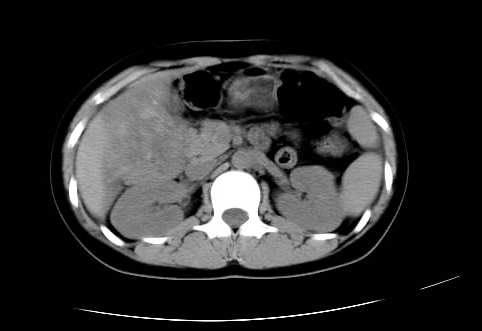

女 16岁  右上腹痛一天,无其他不适

肿块最大径位于十二指肠降段与水平段移行处,并且与肝脏压迹呈“0”形征,可以考虑位于肝外并与胃肠道关系紧密,考虑胃肠道间质瘤(gist)可能较大,须除外神经节起源肿瘤。

肿块与十二指肠关系密切,支持间质瘤诊断.肝脏与结肠均为受压改变.

右下腹巨大肿快,密度不均匀,内见坏死低密度区,边界清楚,与周边胀器明显有分界,未见强化,多考虑来源于间叶组织的良性肿物.

病灶巨大,少部分向肠腔内生长,大部分向长腔外生长。其密度不均匀,增强显示明显不均匀强化,并见有大片状始终不强化的不规则坏死液化区。虽然病灶中上部形态尚可,病人又如此年轻,但中下部形态、密度、强化特点强烈提示为恶性病灶。综上,我考虑本病例为:恶性胃肠道间质瘤。